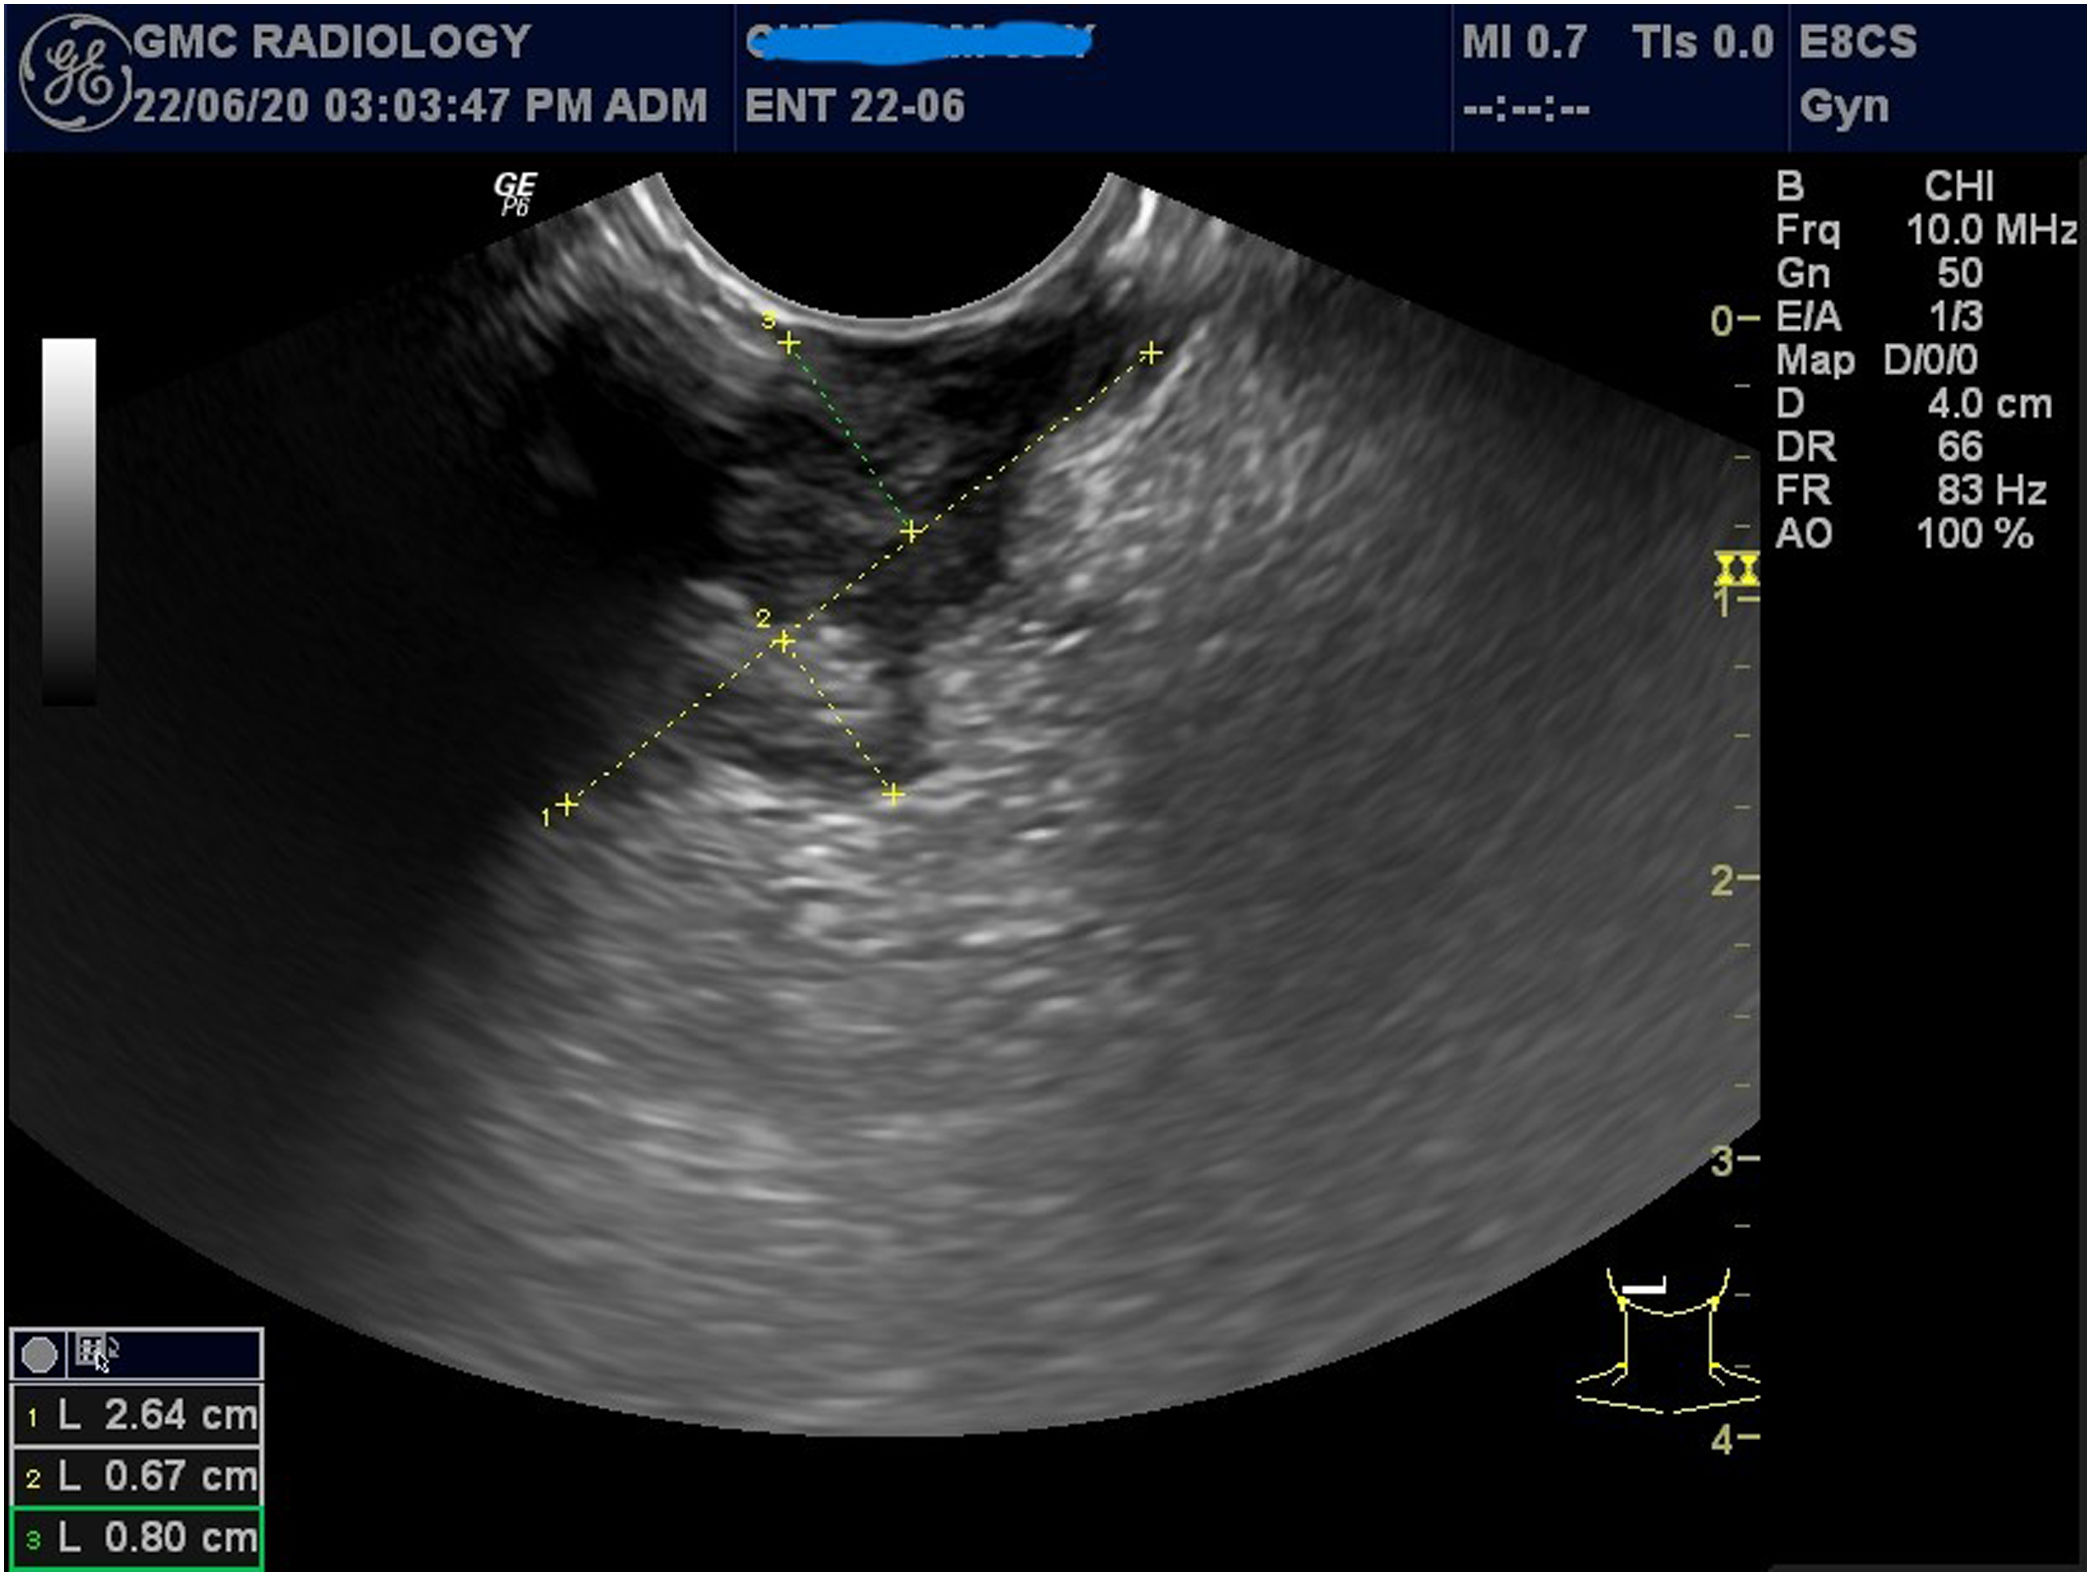

Material and methodsA prospective study was conducted in 30 cases of oral cancer. Subjects were subjected to computerised tomography and intraoral sonography before surgery. The depth of invasion assessed through clinical palpation and radiological tools was compared with surgical histopathology.

ResultsThe depth of invasion assessed on clinical palpation and computerized tomography had statistically significant difference with histopathology whereas intraoral sonography didn’t show any difference. The intraoral sonography and computerised tomography had comparable precision and accuracy, with a slight dominance of the computerised tomography in assessing the tumor's depth of invasion greater than 4 mm. However, intraoral sonography was more precise and accurate than computerised tomography in assessing the depth of invasion beyond 10 mm.